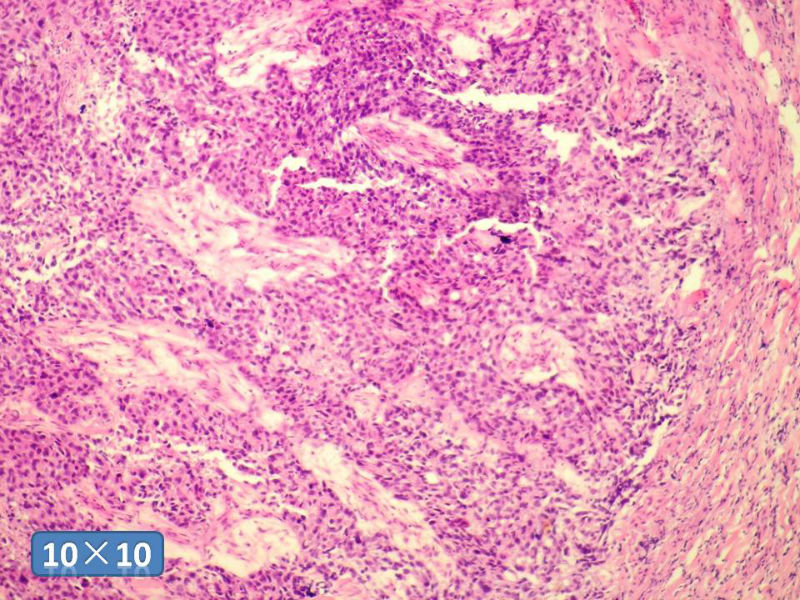

女性,50岁,乳腺肿物,冰冻切片(图1-25)

HE